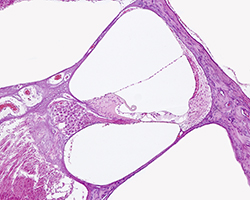

Genital Masculino

Genital Masculino

Testículo, epidídimo, conducto deferente, próstata y vesícula seminal.

(8 preparaciones) -